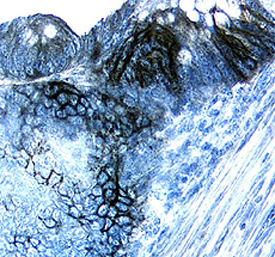

Carbonic Anhydrase IX/CA9 antibody in Human Colon Cancer Tissue by Immunohistochemistry (IHC-P).

Carbonic Anhydrase IX/CA9 in Human Colon Cancer Tissue.

Carbonic Anhydrase IX/CA9 was detected in immersion fixed paraffin-embedded sections of human colon cancer tissue using Goat Anti-Human Carbonic Anhydrase IX/CA9 Antigen Affinity-purified Polyclonal Antibody (Catalog # AF2188) at 15 µg/mL overnight at 4 °C. Tissue was stained using the Anti-Goat HRP-DAB Cell & Tissue Staining Kit (brown; CTS008) and counterstained with hematoxylin (blue). Specific labeling was localized to the plasma membrane of epithelial cells. View our protocol for Chromogenic IHC Staining of Paraffin-embedded Tissue Sections.